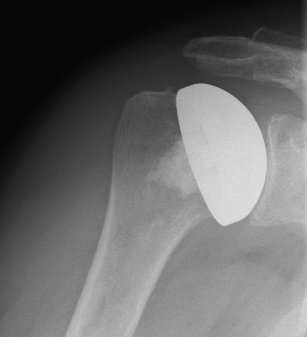

Abbildung2Abbildung1

left: X-ray image of an omarthrosis

right: X-ray of a healthy shoulder joint